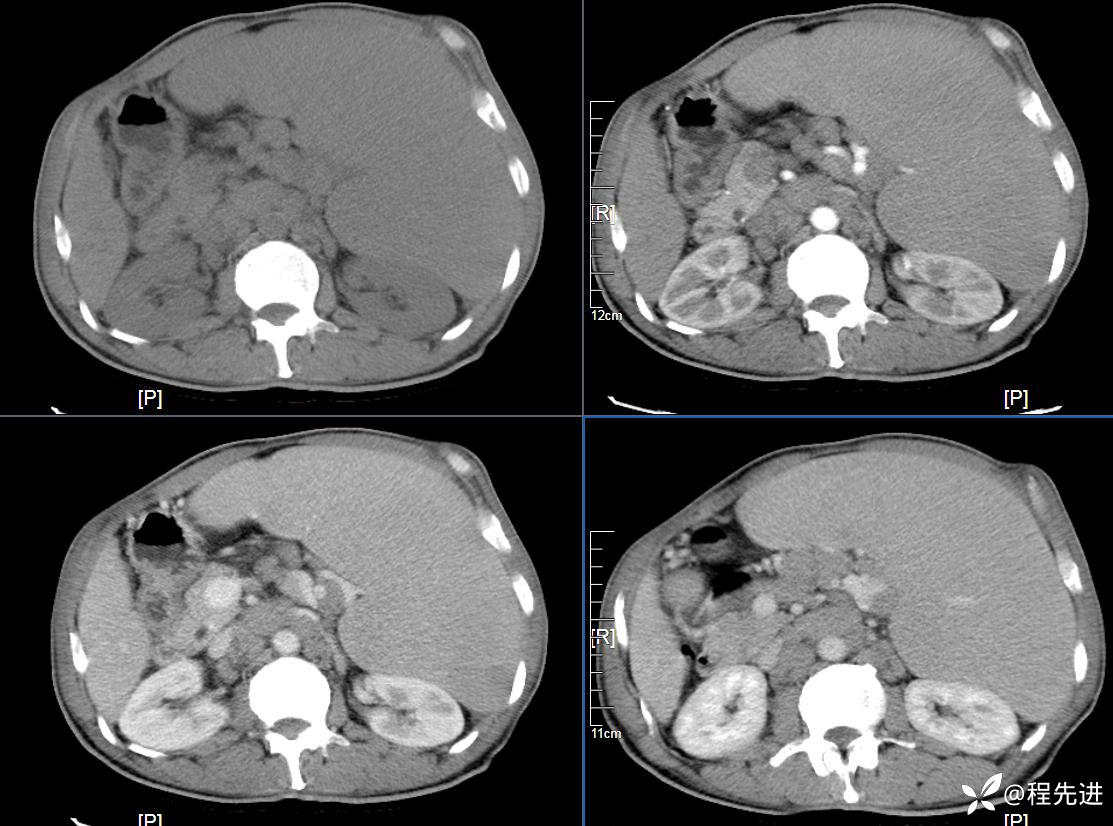

患者性别:男

患者年龄:59岁

简要病史:体检发现脾脏肿大半月

CT平扫及增强3期: